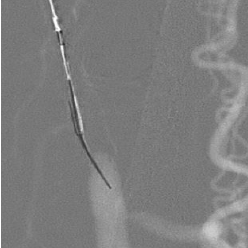

GoBack Crossing Catheter

• 4 different needle protrusion lengths/shapes

• Needle protrusion length selector on handle